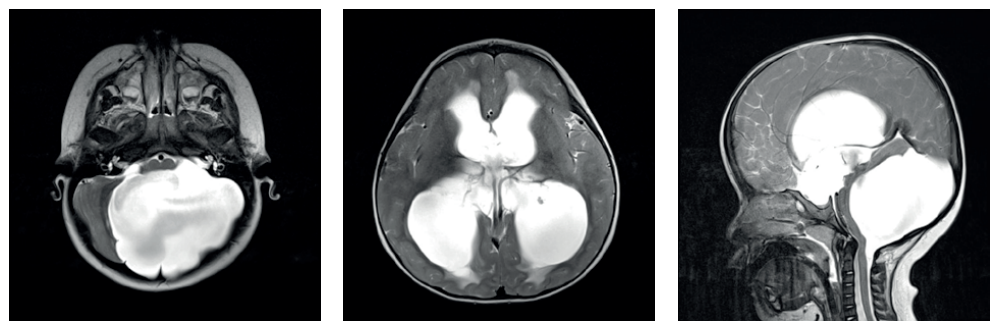

Malformação de Dandy-Walker

A tríade diagnóstica clássica na RM é:

- Hipoplasia ou agenesia do vérmis cerebelar (com rotação cefálica do remanescente).

- Dilatação cística do IV ventrículo.

- Aumento volumétrico da fossa posterior.